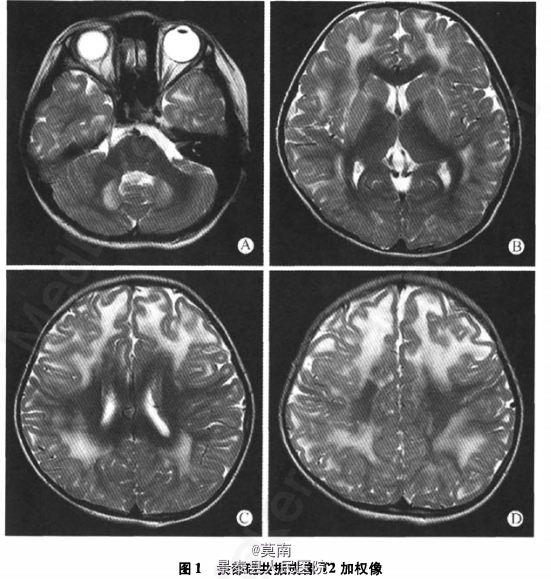

查体:身高110 cm,体质量18 kg,大头畸形,五官正常无畸形。定向力、记忆力、计算力、理解、判断力粗测正常。颅神经检查正常。四肢未见肌肥大、肌萎缩,肌张力对称适中,四肢肌力5-级,腱反射对称活跃,双侧巴氏征阳性。深浅感觉检查未见明显异常。指鼻试验、跟膝胫试验欠稳准。颈软,脑膜刺激征阴性。走直线不稳,能用足跟、足尖行走,Romberg征睁闭眼均稳。皮肤温度湿度正常。 辅助检查:尿有机酸筛查:2一羟基戊二酸(106.74 mmol/mol cre,正常范围0.6~5.9mmol/mol cre)、3一羟基戊二酸(537.83mmol/mol cre,正常范围0)、2一己烯酸(113.02 mmol/ mol cre,正常范围0~16.4 mmol/mol cre)浓度显著高;甘油酸浓度轻度升高。尿液蝶呤分析:正常。血液代谢筛查:精氨酸、瓜氨酸等氨基酸浓度降低,提示营养状况不佳。游离肉碱浓度降低,乙酰肉碱浓度轻度升高,提示继发性肉碱缺乏。血液脂肪酸谱检测:未见典型脂肪酸代谢异常改变;多种脂肪酸浓度降低,提示营养状况不佳。头部MRI:双侧额颞顶枕皮质下白质、双侧小脑、双侧内囊、双侧外囊、双侧放射冠及半卵圆中心可见多发片状长Tl、长12信号影,在FLAIR像上呈高信号影,在b=l 000的弥散加权像上呈高信号影(图1)。

目前患儿症状无明显改善,有待于进一步长期随访观察。2-羟基戊二酸尿症(2-HGA)是一种罕见的常染色体隐性遗传神经代谢障碍性疾病,以血、尿及脑脊液中2-羟基戊二酸(2-HGA)浓度升高为主要特点,并依据构型不同分为D-2一羟基戊二酸尿症(D-2-HGA)和L-2-羟基戊二酸尿症(L-2-HGA)。L-2-HGA在婴幼儿期或儿童期隐袭起病,最初表现为轻度精神运动发育迟缓,随后出现进行性共济失调、智力倒退、癫痫发作、锥体系和锥体外系症状和体征,一半患者出现进行性大头畸形。L-2-HGA神经影像学表现极具特征性,头颅MRI显示散在或弥漫性大脑皮质下白质、基底节(苍白球、尾状核和壳核——按出现频率由多到少)和小脑齿状核长T2信号和脑萎缩,皮质下白质异常呈向心性减轻与其他白质脑病不同。除临床和影像学表现外,明确诊断主要依靠血、尿和脑脊液有机酸分析及异构体分析发现L-2-HGA浓度增高。产前诊断需测量羊水L-2-HGA浓度,仅轻度升高时需强调基因突变分析的重要性。L-2-HGA目前尚无特异性治疗,近2年有报道用维生素B2、FAD和左旋肉治疗可能有效。【摘自:《首都医科大学学报》,2011年2月第32卷第1期,《2-羟基戊二酸尿症病例报道》】